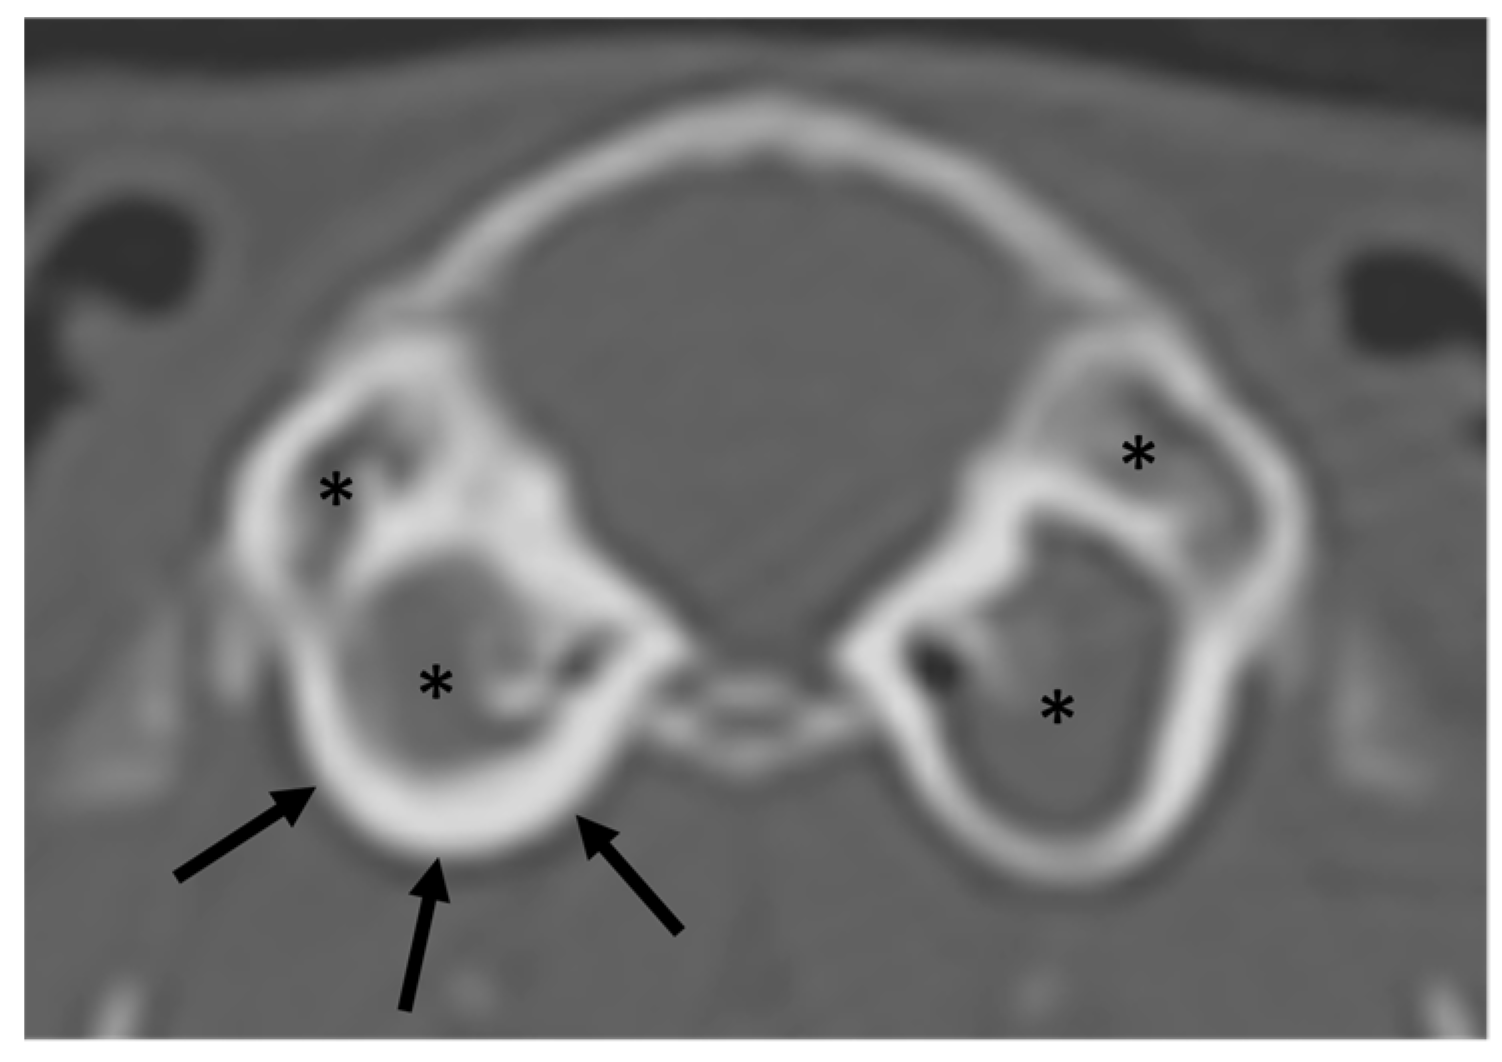

3.2. Guinea Pigs

| Eye | Exophthalmos (1/0) | Deformation (0/0) | Lens luxation (0/0) | Others: mineralization (0/26) |

| TMJ * | Luxation (0/0) | Fracture (0/0) | Deformation (0/5) | Lysis (0/0) |